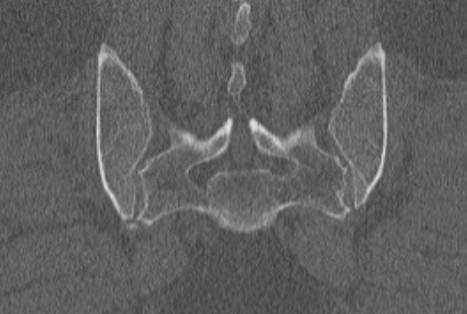

- сужение суставной щели (в норме она составляет 4-5 мм);

- на начальных стадиях заболевания возможно расширение суставной щели;

- на поздних стадиях патологии суставная щель полностью исчезает (полный анкилоз) или на КТ определяются «мостики» из соединительной ткани между суставными поверхностями (частичный анкилоз);

- уплотнение субхондральной (подхрящевой) кости, которое обычно сильнее выражено со стороны подвздошной кости, чем крестца;

- появление кист в субхондральной кости;

- эрозии на суставных поверхностях.